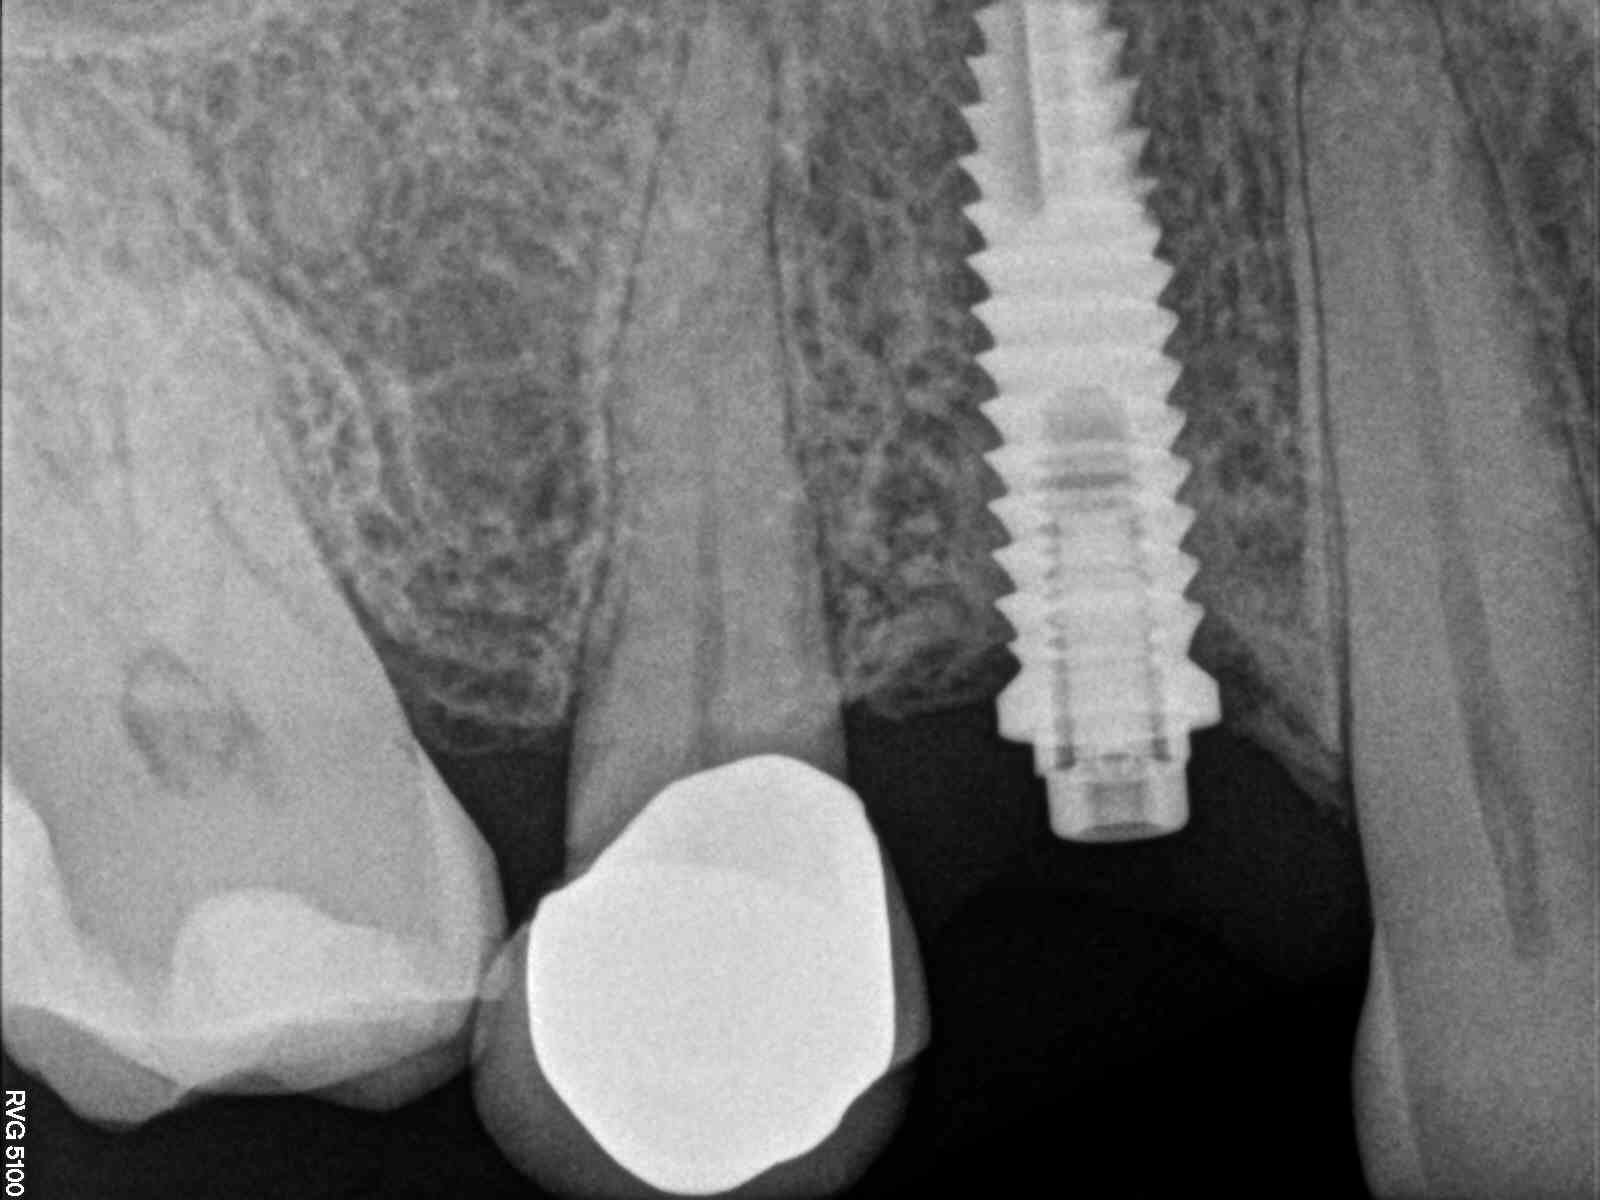

Necesito rehabilitar el 16 y no sé qué marca y modelo es; es Hexágono externo pero de más de 1 mm de alto el mismo y el hexágono del tornillo [...]